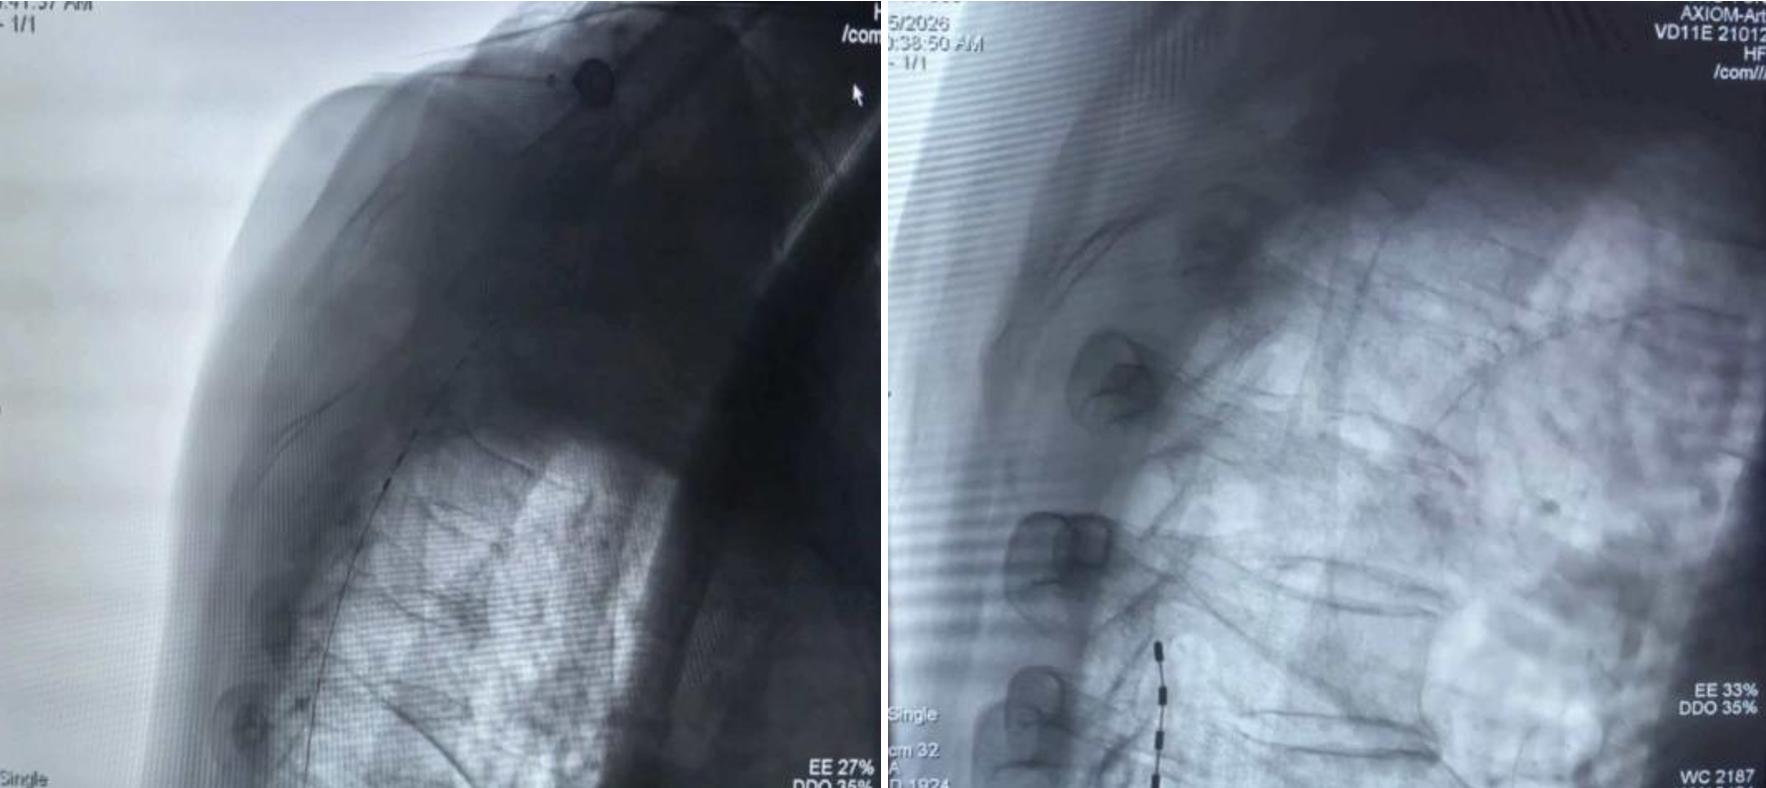

手术中,医疗团队借助DSA数字减影血管造影精准定位,将纤细的刺激电极顺利置入对应疼痛区域的硬膜外腔,全程操作精准、顺利,仅留下微小创口。作为疼痛治疗领域的“绿色疗法”,脊髓电刺激疗法通过电极释放微弱电流,作用于脊髓背柱干扰并阻断疼痛信号向大脑的传递,能显著减少患者对止痛药的依赖,规避药物副作用与成瘾风险,尤其适合高龄、基础病多的患者,实现“减药不减效”的镇痛目标。